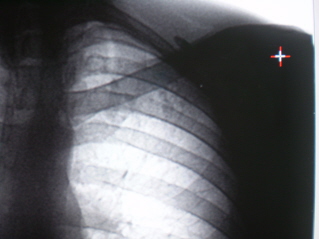

Гражданин С., 35 лет, жалоб не предъявляет. После прохождения профилактической флюорографии (иллюстрации 1, 2) «взят на контроль».

Определяется некоторое усиление и обогащение легочного рисунка в медио-базальных отделах с обеих сторон. Слева под ключицей, на фоне 1 межреберья и 2 ребра определяются очаги средней и малой интенсивности. На фрагменте флюорограммы (с увеличением изображения) не исключается «кавернизация очагов».